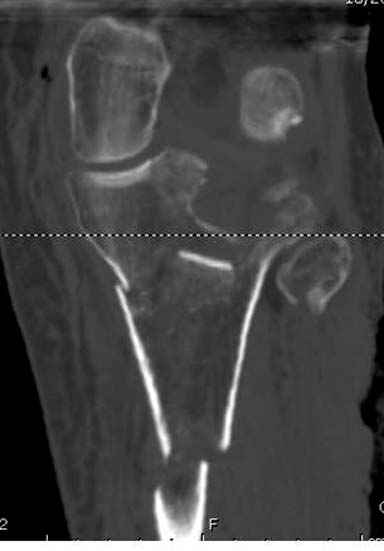

Имелась центральная компрессия. Проводилась артротомия - суставная линия полностью восстановлена. Произведу контрольные рентгенограммы для доказательства.

Спасибо заранее, с интересом посмотрим. Хорошо бы КТ сделать.

Для адекватной оценки необходимо предоставить хотя бы по две проекции до и после синтеза. Снимки после синтеза - с захватом всей длины сегмента т.к. использовался гвоздь. По предоставленной одной некачественной проекции сказать можно только сказать что и решение, и результат спорные.

Отдельные переломы тибиал плато и перелом проксимальной трети большеберцовой кости отличаются от переломов тибиал плато с вовлечением диафиза. Здесь перелом тибиал плато типа Schatzker VI, полученный в результате высокоэнергетической травмы. Перелом метафиза образовал отрыв суставной поверхности от диафиза с вовлечением медиального и латерального мыщелков. Двухмыщелковые переломы из-за укрочения опасны развитием компартаментального синдрома, повреждением латерального мениска и связок.

Если там действительная импрессия, пустое место без структуральных заполнителей, кость или синтетические материалы, не восстановится, а образуется коллапс, и ось конечности поведет после нагрузки. Кроме того там возможно "болт стяжка"?, в медиальной стороне выступает за кортекс, можно было укоротить! Потом создается впечатление, что не соответствуют мыщелки большеберцовой и бедренной костей? Покажите снимок.

Ваша упорство с минимальными данными защищаться забавляет, и пока не все убедились в Вашей правоте. Для нормальной защиты необходимы аргументированные доказательства исследованиями. КТ сканы и прицельно сделанные снимки коленного сустава, а так все аргументы - не более чем "моя фиксация, мне нравится". Без этих доказательств пока только Ваше упорство.....